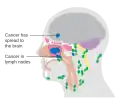

CT Brain showing air-fluid level in bilateral maxillary air sinuses post brain trauma. Maxillary sinusitis will also shows similar air-fluid collection and should be rule out from history taking.

Maxillary sinusitis is inflammation of the maxillary sinuses. The symptoms of sinusitis are headache, usually near the involved sinus, and foul-smelling nasal or pharyngeal discharge, possibly with some systemic signs of infection such as fever and weakness. The skin over the involved sinus can be tender, hot, and even reddened due to the inflammatory process in the area. On radiographs, there is opacification (or cloudiness) of the usually translucent sinus due to retained mucus.[9]